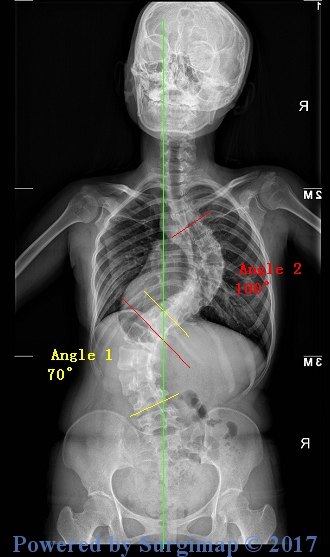

接下来的脊柱X光照片显示了畸形的严重性,胸弯达到了100°,腰弯也有70°:

手术的效果是显而易见的,胸弯腰弯的角度从100°和70°分别矫正到22°和20°!